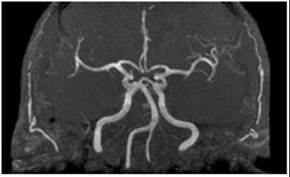

Los vasos del polígono de Willis a menudo parecen engrosados. El estrechamiento de la luz y los depósitos intracelulares en arterias y arteriolas son hallazgos adicionales.19 La dolicoectasia de las arterias basilar y vertebral, y menos frecuente de las arterias carótidas, es un hallazgo constante tanto en homocigotos como en heterocigotos sintomáticos.25

La dolicoectasia encontrada con frecuencia en la EF, particularmente en los grandes vasos de la circulación posterior, puede estar relacionada con el debilitamiento mecánico de la pared del vaso, causado por el depósito de glucoesfingolípidos y la hipertensión. Los mecanismos fisiopatológicos de la EVC asociados a la dolicoectasia incluyen la formación de émbolos y oclusión de arterias penetrantes del tallo cerebral. La afectación cardíaca en la EF también puede predisponer a la EVC, principalmente su asociación con arritmias.9